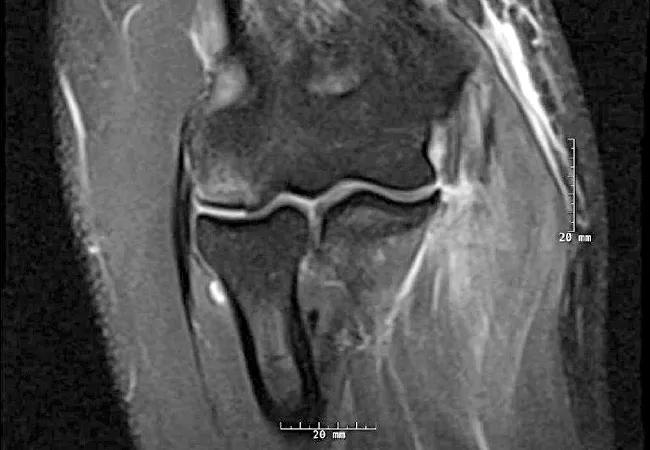

For the first time, a group of trained specialist surgeons from different institutions is able to identify complete versus partial tears and tear location in injuries to the ulnar collateral ligament (UCL).

A new study will be presented today at the 2019 Annual Meeting of the American Association of Orthopaedic Surgeons (AAOS) and Saturday, March 16, 2019 at American Shoulder and Elbow Society (ASES) Specialty Day in Las Vegas, which evaluates the reliability and reproducibility of a newly proposed 6-stage, MRI-based classification system for UCL injuries. The classification system takes into account tear grade (partial or complete) and location (proximal, midsubstance or distal) for broad generalizability and communication in future research.

Compared to intraoperative findings, observers had high accuracy rates for partial and complete grade tears (90%), proximal tears (100%) and distal tears (64%). Observers had much lower accuracy (40%) for midsubstance tears. This shortcoming may be of little clinical significance in light of the system’s overall utility in the accurate identification of proximal versus distal tears, as proximal tears may be more amenable to a nonoperative approach while distal tears tend to require surgical intervention. With near perfect intraobserver reliability and substantial agreement with interobserver reliability, these preliminary results pave the way for validation studies.

Additional axial views did not increase agreement within and among reviewers, indicating that the view of choice is coronal. In order to classify a tear, the axial or sagittal view may not be necessary.

Magnetic resonance arthrography (MRA) is gold standard evaluation; however, MRI is also considered a valuable, noninvasive method of evaluation for UCL injuries. A similar study, which assesses the reliability of this classification system using MRA imaging, is forthcoming.